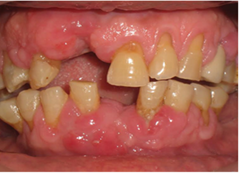

Caso clínico 2

Paciente de sexo masculino de 65 años de edad quien refirió en la consulta odontológica sobrecrecimiento gingival en maxilar superior e inferior. Manifestó tener antecedentes de epilepsia hace aproximadamente 8 años, tratada con fenitoína (difenilhidantoína) 300mg/12 horas.

Al realizar examen clínico se observó aumento del volumen de la encía marginal y papilar y encía adherida tanto en maxilar superior como inferior, de aspecto lobulado, y de color rojo intenso. Ausencia de OD# 11, 31; múltiples recesiones gingivales en OD# 13, 12, 21, 22, 23, 32, 34, 35, 44, 45 de aproximadamente de 3 a 6 mm. Además, se pudo evidenciar el acúmulo de placa bacteriana presente en las superficies interproximales de OD# 13, 32, con un índice de placa bacteriana de 30% según el índice de O'lear 13) (Figura 2). El procedimiento quirúrgico se realizó sin complicaciones.